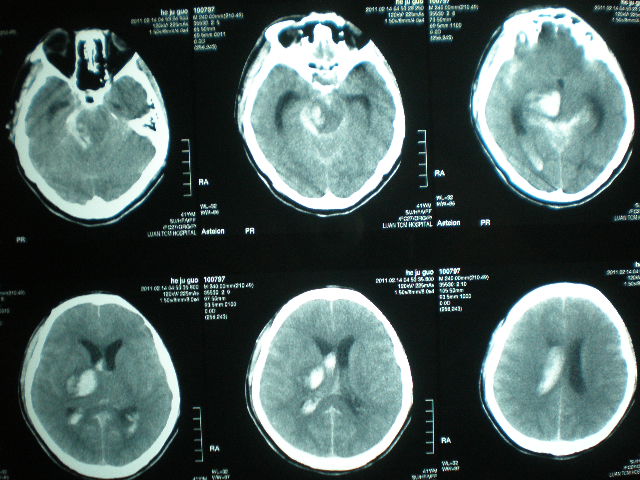

病例一

患者徐某某 、女、55歲、家住濰坊市經(jīng)濟(jì)開(kāi)發(fā)區(qū)馬家埠村。2008年3月5日,患者被家屬發(fā)現(xiàn)突然意識(shí)不清,呼之不應(yīng),惡心、嘔吐,右側(cè)肢體癱瘓。由120車(chē)接到市立醫(yī)院。做顱腦CT后診斷“腦出血”。及時(shí)做腦出血微創(chuàng)手術(shù),病人轉(zhuǎn)危為安。12天后病人能自己吃飯、穿襪子、穿鞋,自己走出病房出院。病人及家屬送錦旗表示感謝。

病例二

患者玄某某、女、90歲,家住濰坊市經(jīng)濟(jì)開(kāi)發(fā)區(qū)邢石村。2014年3月13日,患者突然感到眩暈,之后重重摔倒在地,出現(xiàn)昏迷,家屬發(fā)現(xiàn)后撥120,120急救車(chē)將患者接到市立醫(yī)院?;颊叱霈F(xiàn)呼吸不規(guī)整,有時(shí)呼吸暫停,瞳孔不等大,瀕臨死亡的邊緣。做顱腦CT后診斷“腦出血”。當(dāng)即決定做腦出血微創(chuàng)手術(shù)。10天后患者意識(shí)清醒,出院。

? 1、病人頭部備皮,閱讀腦出血病人第一張顱腦CT片,以CT片OM線(xiàn)為基線(xiàn),畫(huà)出腦出血最大出血層面在頭皮的位置線(xiàn),在此線(xiàn)上測(cè)出前額至血腫中心的距離,初步確定穿刺到達(dá)血腫中心在顱腦頭皮位置點(diǎn)。并貼金屬片做標(biāo)記。

? 2、手術(shù)前再做一次顱腦CT,以觀(guān)察血腫有無(wú)增大。觀(guān)察初步確定的穿刺點(diǎn)是否準(zhǔn)確,再次做調(diào)整,確定頭皮穿刺點(diǎn)。